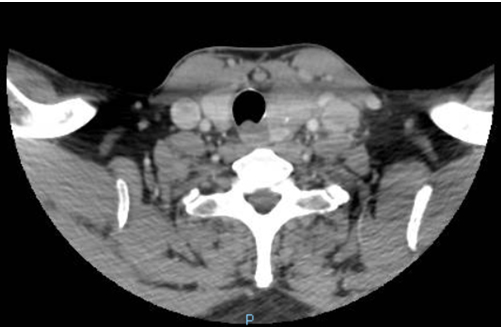

Figure 3. The crescent trachea sign with apparent double-lumen (the posterior lumen is the oesophagus)

(CT scan)